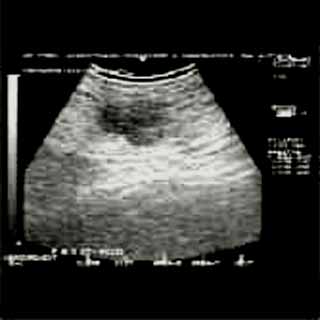

Οι απεικονίσεις των περιστατικών που επιδεικνύονται παρακάτω, έγιναν με κυρτές κεφαλές 3,5 και 5 ΜΗΖ, προκειμένου να φανεί, ότι και με τον εξοπλισμό αυτό, που σιγά-σιγά διαθέτουν όλο και περισσότερα ιατρεία, είμαστε σε θέση να έχουμε ικανοποιητικά αποτελέσματα.

Oι τελευταίες 4 απεικονίσεις έγιναν με ειδικό για μαστό ηχοβολέα linear, εναλλασσομένης συχνότητος 7,5-10ΜΗΖ.